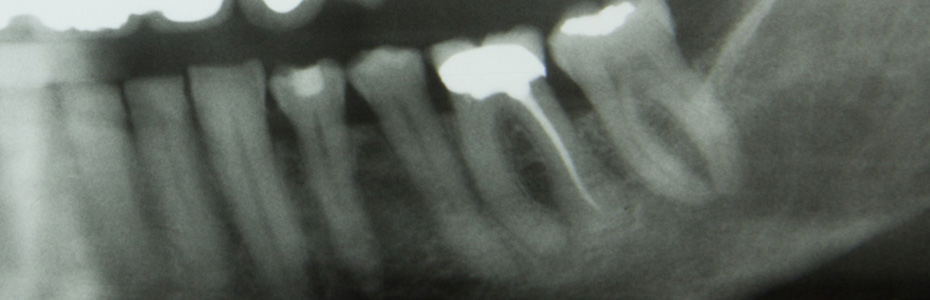

Les dents de sagesse complètement sorties et correctement positionnées posent généralement peu de problèmes. La plupart du temps, l’espace disponible ne suffit pas. Les dents de sagesse décalées (mauvais alignement) ou seulement partiellement sorties causent des dommages au reste de la dentition existante. A l’endroit des avancées, des inflammations de la gencive ou des abcès douloureux peuvent se produire causés par une hygiène buccale rendue difficile. Lors de l’extraction de dents de sagesse profondément ancrées dans l’os, les structures anatomiques voisines, le tissu et les nerfs doivent être épargnées. L’extraction de plusieurs dents de sagesse peut être effectuée en une opération. Les impératifs médicaux définissent combien les dents de sagesse peuvent être enlevées et à quel moment.